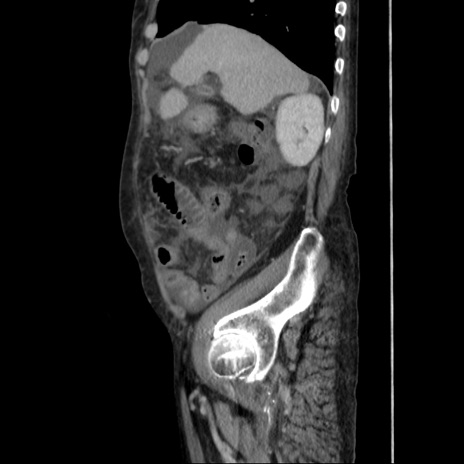

症例31(矢状断像)

【症例】80歳代 女性

【主訴】腹部膨満感

【現病歴】他院にて肝硬変にてフォロー中。1週間前から便秘、腹部膨満感、臍部腫瘤あり受診となる。

【既往歴】肝硬変

【身体所見】腹部膨隆あり、皮膚変化なし、疼痛なし。

【データ】WBC 4600、CRP 0.25